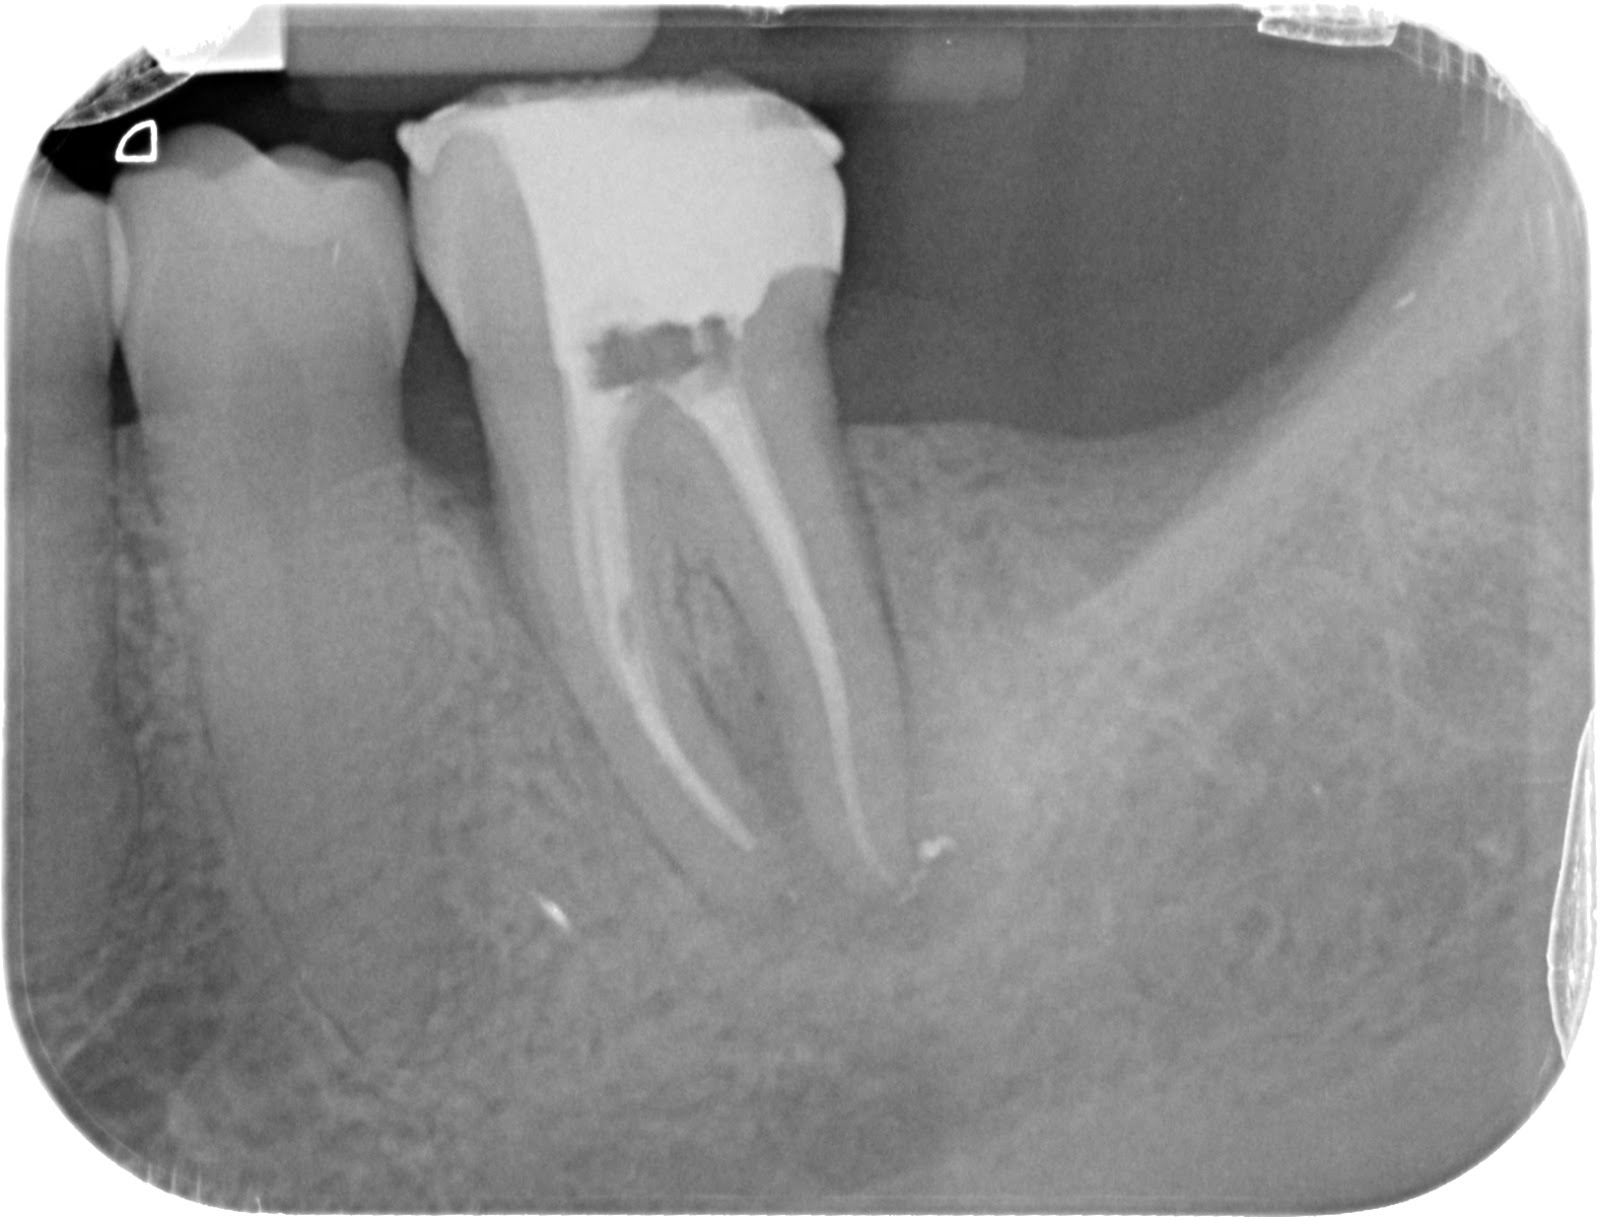

Sellamos la comunicación vestibular con Cavit, realizamos apertura con fresa H7, aislamos con clamp nº9 y localizamos dos conductos, uno vestibular y otro lingual.

Permeabilizamos con limas K#10 y #15 y expandimos el glidepath de forma rotatoria con la lima R-Pilot (VDW). Medimos los conductos con nuestro LEA (En este caso Propex Pixi), obteniendo unas longitudes de 18mm (V) y 19mm (L).

Para la instrumentación del conducto usamos Protaper Next X1 y X2. Una vez instrumentados, realizamos el protocolo habitual de irrigación con NaOCl 4’25%, EDTA 17% y NaOCl 4’25% activado durante 30 segundos por conducto con Endoactivator.

Secamos con puntas de papel, calibramos el conducto, y obturamos con Autofit .06 y condensación vertical en caliente, con el sistema B&L.